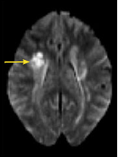

Gregory W. Rutecki, MD; Catherine Manolakis, MD; Charles I. Bie, MD

<p><img src="/sites/default/files/images/May_MRI_Scan_2011.jpg" style="float: left; margin-left: 8px; margin-right: 8px;" height="135" width="100">A...